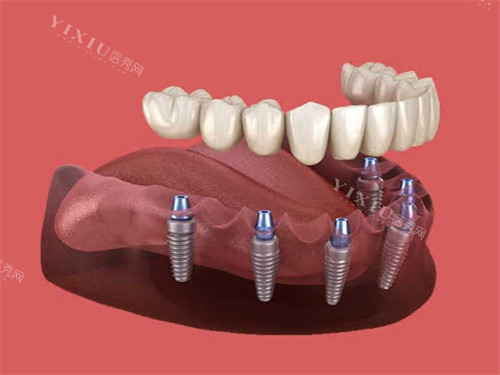

55 岁的刘先生,因意外导致一颗门牙缺失,不仅影响美观,还让他在进食时感到不便。在对比多家口腔机构后,他选择了株洲德堡口腔进行种植牙手术。“我之前担心种植牙手术复杂、改善时间长,但德堡口腔的医生打消了我的顾虑。” 刘先生说道。

种植团队通过 CBCT 影像设备,对刘先生的牙槽骨情况进行了精细评估,结合他的身体状况,制定了即刻种植方案。“医生详细讲解了即刻种植的优势,当天拔牙当天种牙,能缩短治疗周期,减少痛苦。” 手术过程中,医生操作娴熟,配合默契,仅用了 1 个多小时就完成了种植手术。

术后,医护人员不仅为刘先生准备了详细的术后护理手册,还反复叮嘱注意事项,并定期进行电话回访。如今,刘先生的种植牙使用了半年多,他满意地表示:“这颗种植牙就像自己的真牙一样,吃东西完全没问题,外观也很自然,真心感谢株洲德堡口腔!”